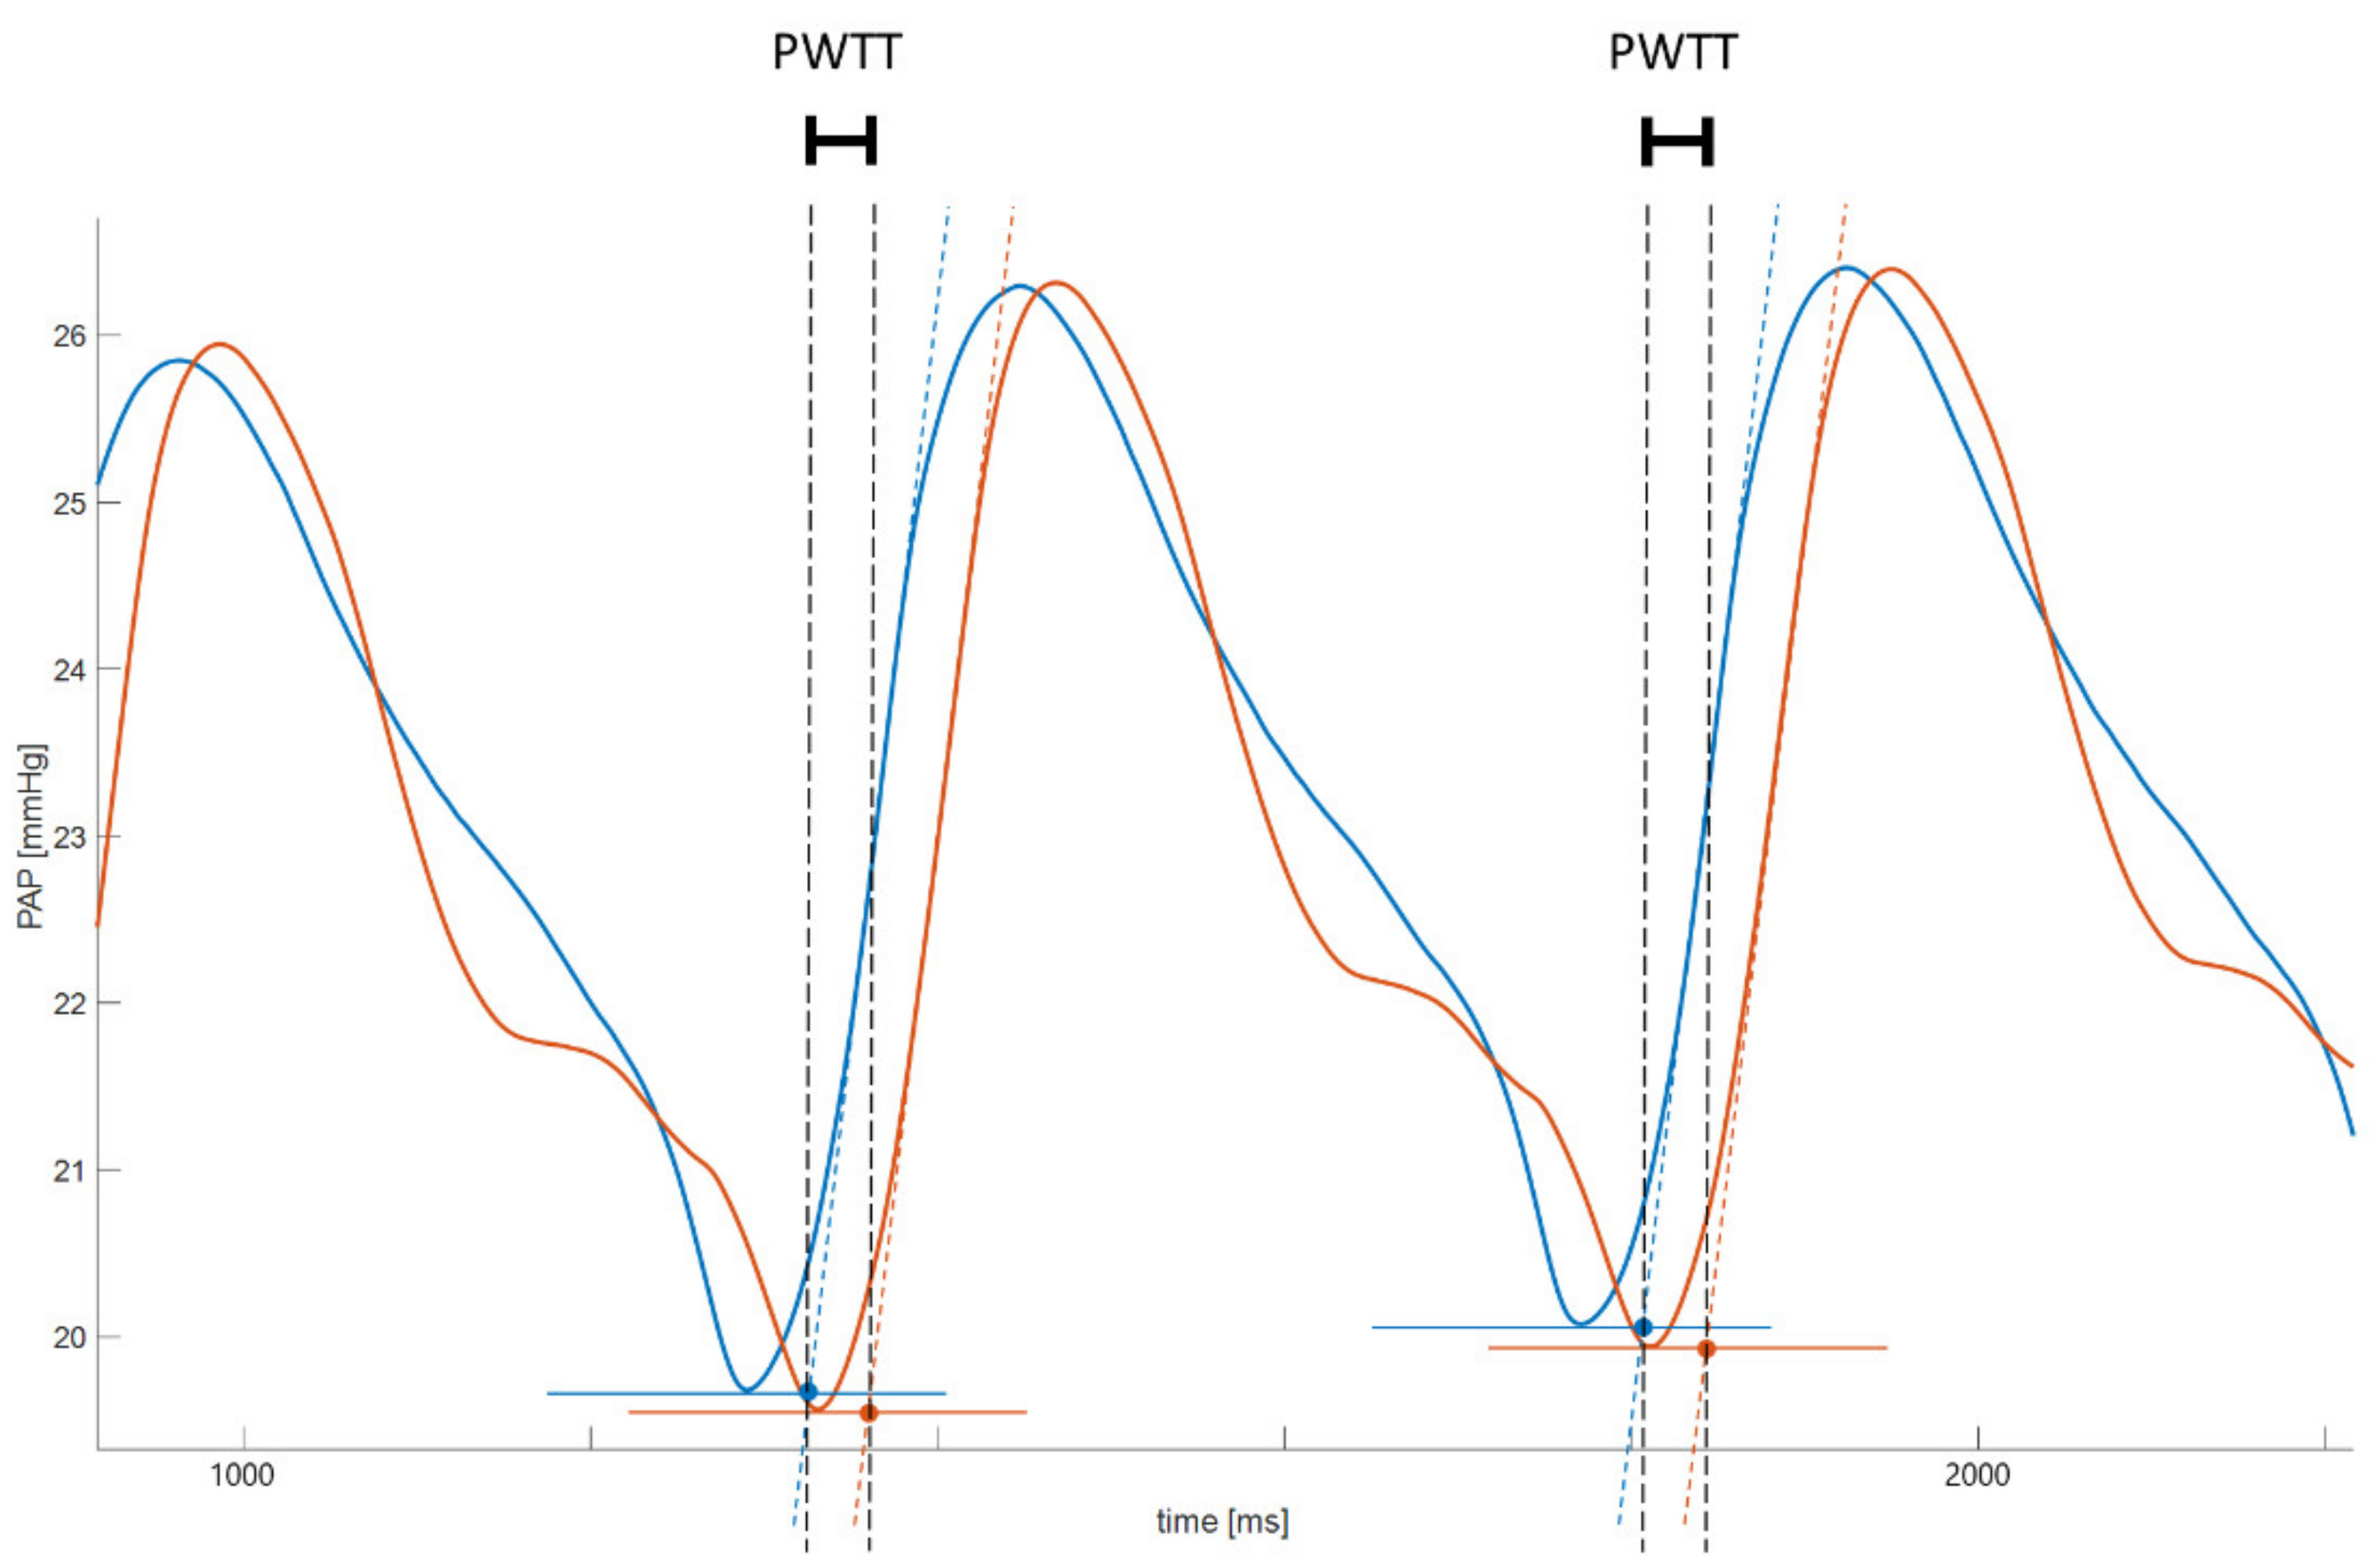

2.4. Data Acquisition and Processing

3. Results